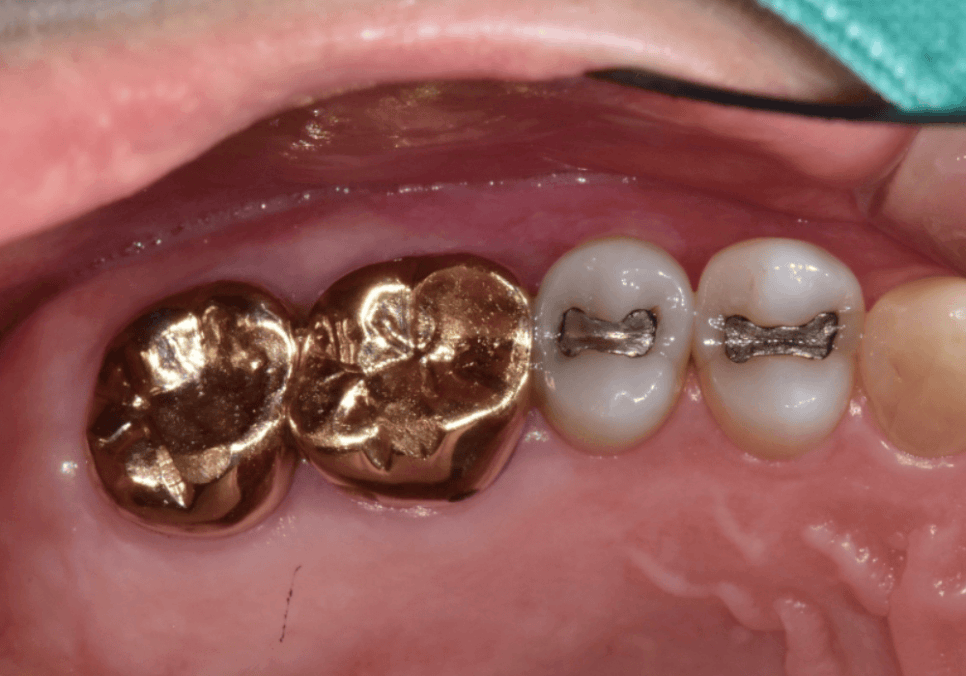

최근 저희 치과를 찾으신 환자분은

왼쪽 아래 작은 어금니가 부러진 상태로 오셨습니다.

오래전 치료받은 아말감이

조금씩 떨어져 나갔는데,

통증이 없다 보니 그냥 사용하셨다고 해요.

하지만 정밀 검사를 해보니

상황은 생각보다 심각했습니다.

아말감 아래로 2차 충치가

아주 깊게 진행되어 있었거든요.